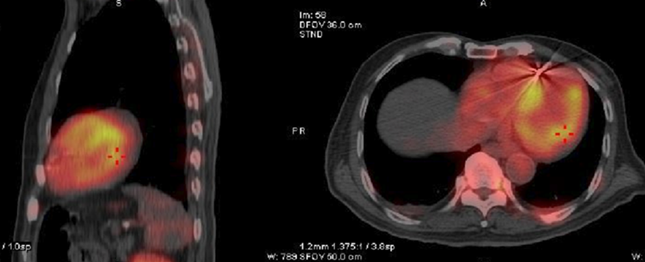

▲核医学科心肌核素pyp显像结果,是检测ATTR-CM的重要手段

心内科专家团队通过进一步完善检查,使用了包括血清免疫球蛋白、核素、基因检测等一系列精准的诊断手段,通过精准流程,步步深入,最终,多份检查结果指向了一个结果——张爷爷患上的是野生型ATTR-CM(转甲状腺素蛋白淀粉样变性心肌病),这是心肌淀粉样变性的其中一种,也是浙江省确诊的首例野生型ATTR-CM。

“随着诊断技术的不断进步,有些曾经被认为是罕见病的疾病,很可能只是缺乏早期精准诊断方式。这些年,我们临床发现不少曾被诊断为缺血性心肌病、心衰、心肌肥厚等疾病的患者,其实可能背后都是因其他疾病引起的。如果不找到确切的病因,肯定会影响预后。”心内科主任郭晓纲主任医师说,2019年,浙大一院核医学科在省内率先开展心脏99mTc标记的焦磷酸(PYP)核素显像。多项临床研究表明,PYP核素检测诊断ATTR-CM的精准度达到90%以上,这是诊断ATTR-CM的非常有力手段。多项临床研究表明,PYP核素检测诊断ATTR-CM的精准度达到90%以上,这是诊断ATTR-CM的非常有力手段。